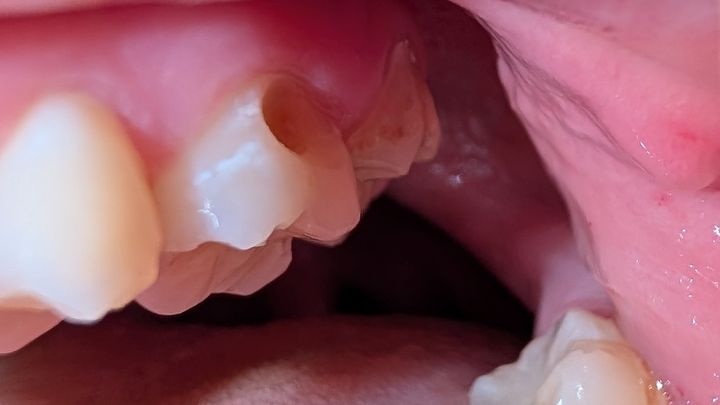

This all started with needing a few fillings and has snowballed into something much much worse. I've already been to the ER with pulpitis once and I couldn't afford it, and I may have to go again. I'm suffering daily headaches and sensitivity and it's hard to enjoy eating or drinking, let alone get out of bed.

I just need some help. I'm trying to get insurance to cover the root canals but they won't budge, and since I can't afford any better insurance and can't get enrolled in my job's insurance until October, it's even harder.